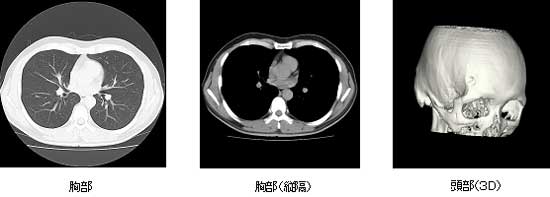

当クリニックでは、最新型の16列全身用コンピュータ断層撮影装置 Revolution ACTを使用しています。

CT 検査による画像例